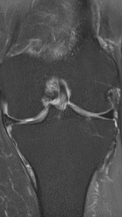

Асептический некроз коленного сустава

4 процедуры ФДТ, 9 процедур MBST, 15 процедур ИПМТ

Параметры изменяются в зависимости от процедуры

Дата публикации: 22.08.2025 14:27:03

3 процедуры ФДТ, 9 процедур MBST, 15 процедур ИПМТ

Дата публикации: 22.08.2025 14:26:54

Рецидивирующий синовит коленного сустава

Излечение за 1 процедуру ФДТ Ревиксан

Рецидивирующий бурсит коленного сустава

Излечение за 2 процедуры ФДТ Ревиксан